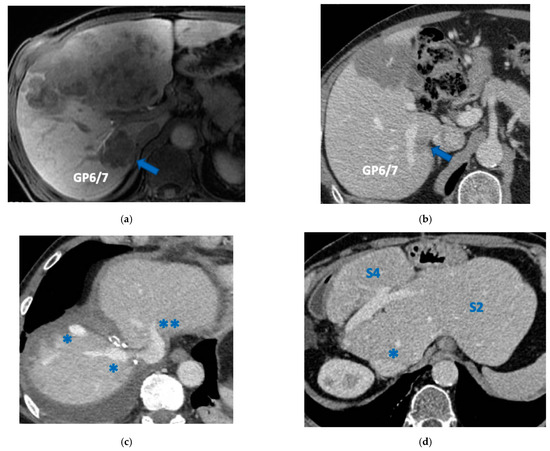

Figure 6. CT Images of PS-TSH with SS-PVE performed to treat 35 bilateral CRLMs. (a) Partial response after FOLFOXIRI + Bevacizumab 12 cycles; FLR (=S2/S3) volume is 15%. (b) Blue arrow points GP 5 after the first stage consisting of resection of S1/S4 extended to S2/S8/S5 plus metastasectomy of S2 with tangential resection of LHV. (c) Fourteen days after stage 1 SS-PVE was performed on the right liver preserving GP 5 (blue arrow); 37 days after SS-PVE FLR (=S2/S3/S5) increased up to 37%. (d) Blue arrow points GP 5. Twenty-five months after PS-TSH with SS-PVE the patient is disease free; the liver’s only disease recurrence was successfully treated with another 3 liver resections (2 on the right liver and 1 on the left). Abbreviations: PS-TSH: parenchyma-sparing TWO-STAGE hepatectomy; SS-PVE: super-selective portal vein embolization; CRLM: colorectal liver metastases; FLR: future liver remnant; S: segment; GP5: glissonean pedicle for segment 5; LHV: left hepatic vein.